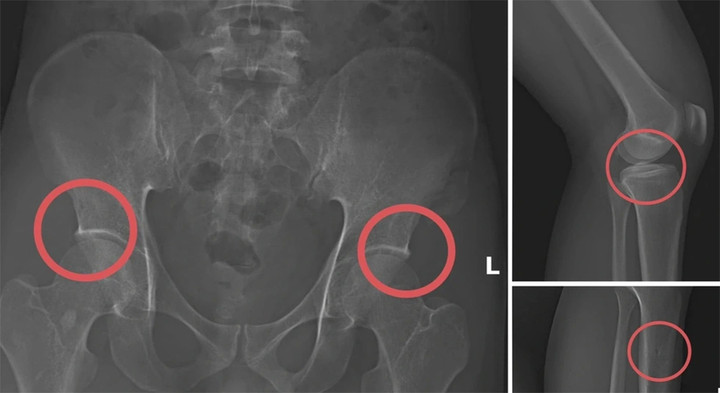

Bản phim chụp X-quang một số tổn thương xương do đối tượng Tạ Minh Châu tạo ra.

Tại đây, Châu tiêm thuốc mê vào tĩnh mạch tay phải của người mua bảo hiểm, sau khoảng 1 phút họ bị mê đi thì Châu sẽ dùng búa và kim tiêm đục, đâm vào vùng cơ thể đã thống nhất từ trước để tạo vết tổn thương trên xương cho nứt, vỡ (thường sẽ làm rạn nứt, vỡ vùng xương chậu, xương đùi…).

Khoảng 10-20 phút khi thuốc mê hết tác dụng, những bệnh nhân tỉnh lại, Châu hướng dẫn những người này tạo ra những vụ tai nạn tự nhiên để được hưởng bảo hiểm như: Bị điện giật ngã làm nạn nhân gãy xương chậu, đi suối ngã gãy chân... rồi nhờ người đưa đến Trung tâm Y tế, bệnh viện khám và điều trị lấy bệnh án.